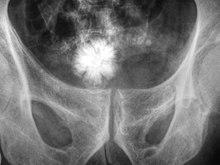

A star-shaped Jackstone urolith can be seen in the urinary bladder on this radiograph of the pelvis

Jackstone calculi are rare bladder stones that have an appearance resembling toy jacks. They are almost always composed of calcium oxalate dihydrate and consist of a dense central core and radiating spicules. They are typically light brown with dark patches and are usually formed in the urinary bladder and rarely in the upper urinary tract. Their appearance on plain radiographs and computed tomography in human patients is usually easily recognizable. Jackstones often must be removed via cystolithotomy.[10]